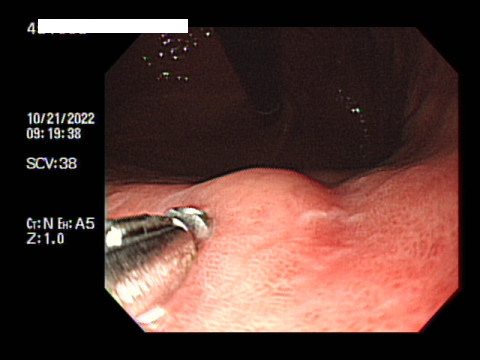

겨우 아침 9시 반에 병원에 도착해서 위내시경실로 바로 갔는데 혼자 왔다는 이유로 수면 내시경은 안된단다. 당연히 될거라 생각했는데 절대 안된단다. 보호자가 동반해야지 수면이 가능하다고 해서 결국 비수면으로 했다. 난생처음.. 지옥을 맛봤다. 게다가 환자동의서를 받은 과정에서 좀 무서운 이야기를 막 해대서 이건 뭐 위 내시경 받다가 응급실 가는 거 아닌가 걱정이..

그렇게 팔뚝에 X나 아픈 진경제 주사를 맞고, 세상 맛없는 입과 목을 마취해주는 약을 입안에 3분간 넣고 삼키며 점점 마비되어가는 입과 목 그리고 식도의 불쾌감을 참고 기다리고 있는데 3번 검사실로 불려갔다.

옆으로 누워서 간호사의 설명을 듣고 마음의 준비도 안되었는데 이건 마치 도살장에 끌러온 소마냥.. 흑흑

입에 재갈을 물리고 드러누워 꼼짝 못하는데 눈앞에서는 불빛을 부라리면서 곧장이라도 내 입안으로 들어올 듯한 꽃 뱀같은 내시경을 보고 있도라니 정말 너무 무서웠다.

결국엔 검사하는 내내 너무 힘들게 받았다. 뱀처럼 긴 내시경이 내 위장을 후비고 있을 때 극한의 구역질의 고통속에서 스스로 이렇게 누워있는 내 자신이 참 딱하게 느껴졌다. 이런 검사를 받고있는 것도 기가막힌데.. 힘들게 받고 있자니. 서글프다.